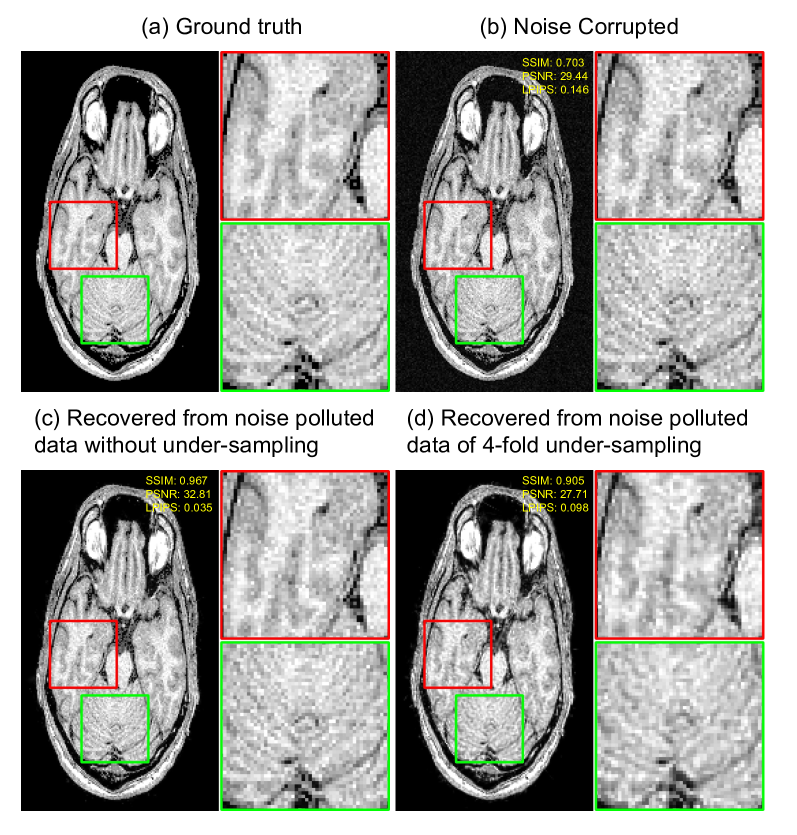

IV-E Noise resistance characteristics of 3DGSMR

It is observed that 3DGSMR could effectively reduce noise in the reconstruction. In this section, we present results demonstrating the noise resistance capabilities of the proposed framework. We manually add noise sampled from Gaussian distribution to the acquired k-space to simulate the noise scenario. The reconstruction results are shown in Figure 7. It can be observed that the noise has been effectively reduced, while the texture details are well-preserved.

Refer to caption

Figure 7: Visual comparison of the reconstructed images from noise-corrupted data, assessed using SSIM, PSNR, and LPIPS. The third image shows the recovery without undersampling, while the fourth image demonstrates recovery from 4-fold undersampling.